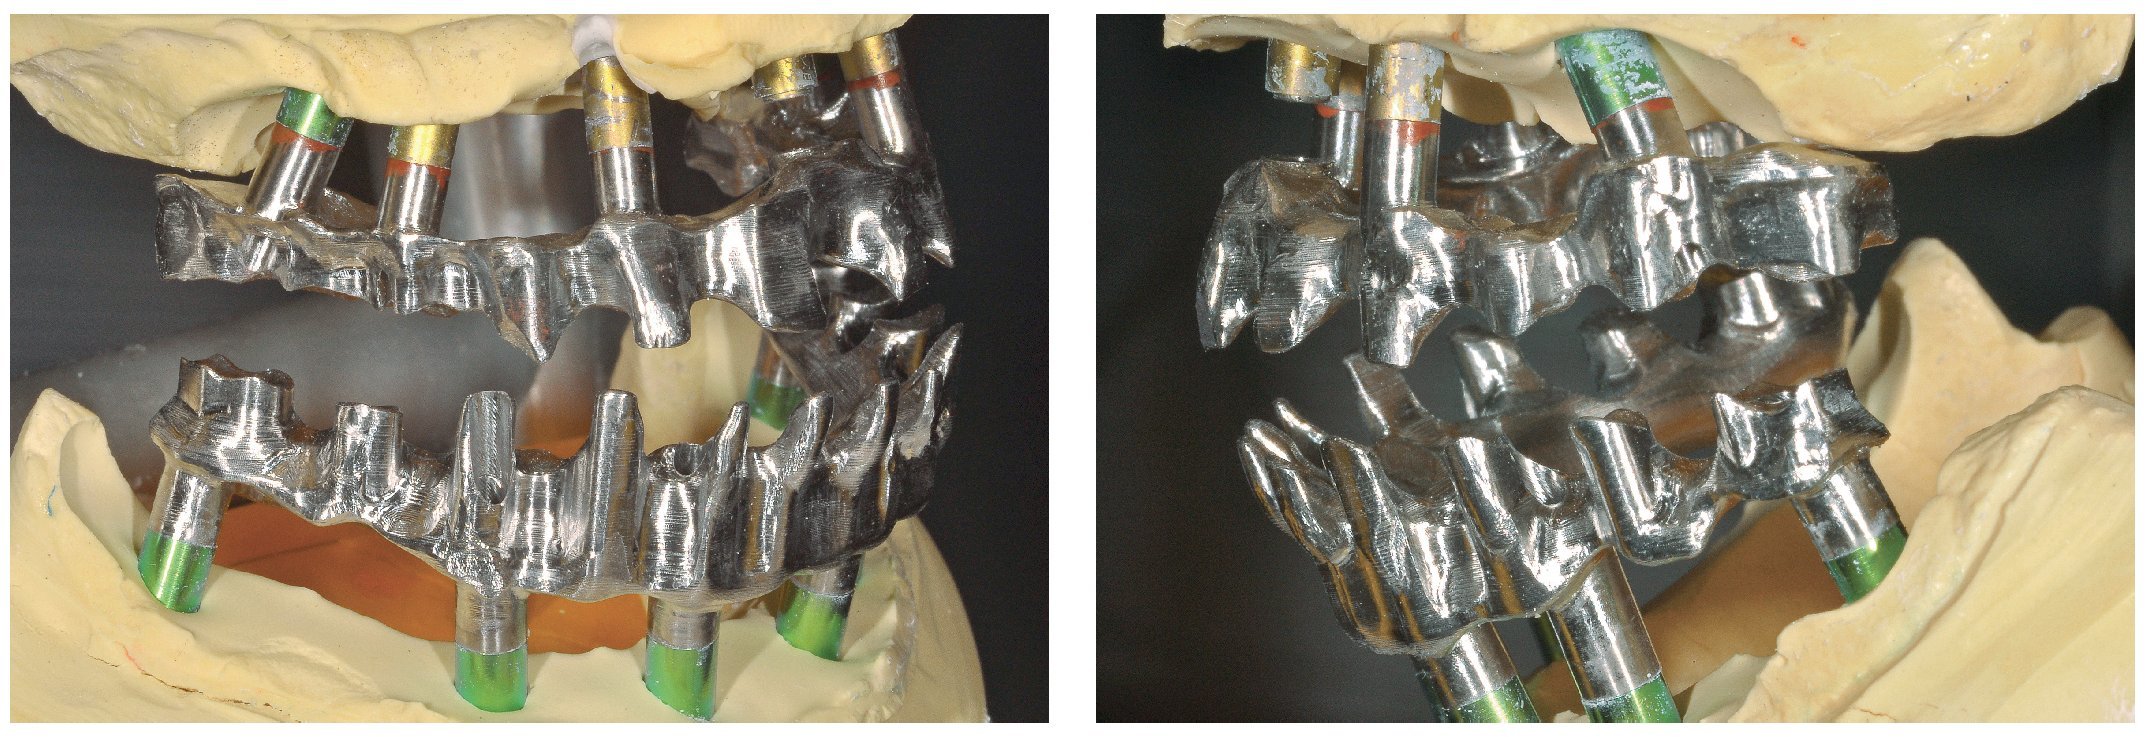

Pese a ello, es importante someter las estructuras a un control visual y mecánico, a fin de corregir eventuales discrepancias menores (figs. 99 a 102). A continuación se procede al montaje utilizando dientes protésicos prefabricados de composite (SR Phonares NHC, Ivoclar Vivadent, Ellwangen, Alemania), los cuales reproducen el tipo funcional correspondiente en virtud de sus propiedades morfológicas y estructurales y se integran armoniosamente en cuanto a su longitud dental (figs. 103 a 105). Durante la comprobación de las restauraciones protésicas, se evalúan clínica y radiológicamente ante todo la pasividad y la precisión del ajuste de la estructura. Acto seguido se lleva a cabo una comprobación de la oclusión y de la dimensión vertical, del estado de las prótesis y del tejido blando en la cresta alveolar, así como la verificación del espacio libre lingual, incluida la fonación, y el apoyo de los labios y las mejillas (figs. 106 y 107). También se debe comprobar la facilidad de higiene de la restauración de acuerdo con las habilidades manuales del paciente. A continuación se debe verificar la posición tridimensional de los dientes anteriores con los labios cerrados y durante la sonrisa, así como el aspecto global de la rehabilitación protésica.

Figs. 101 y 102. Vista lateral de las estructuras atornilladas sobre los modelos.